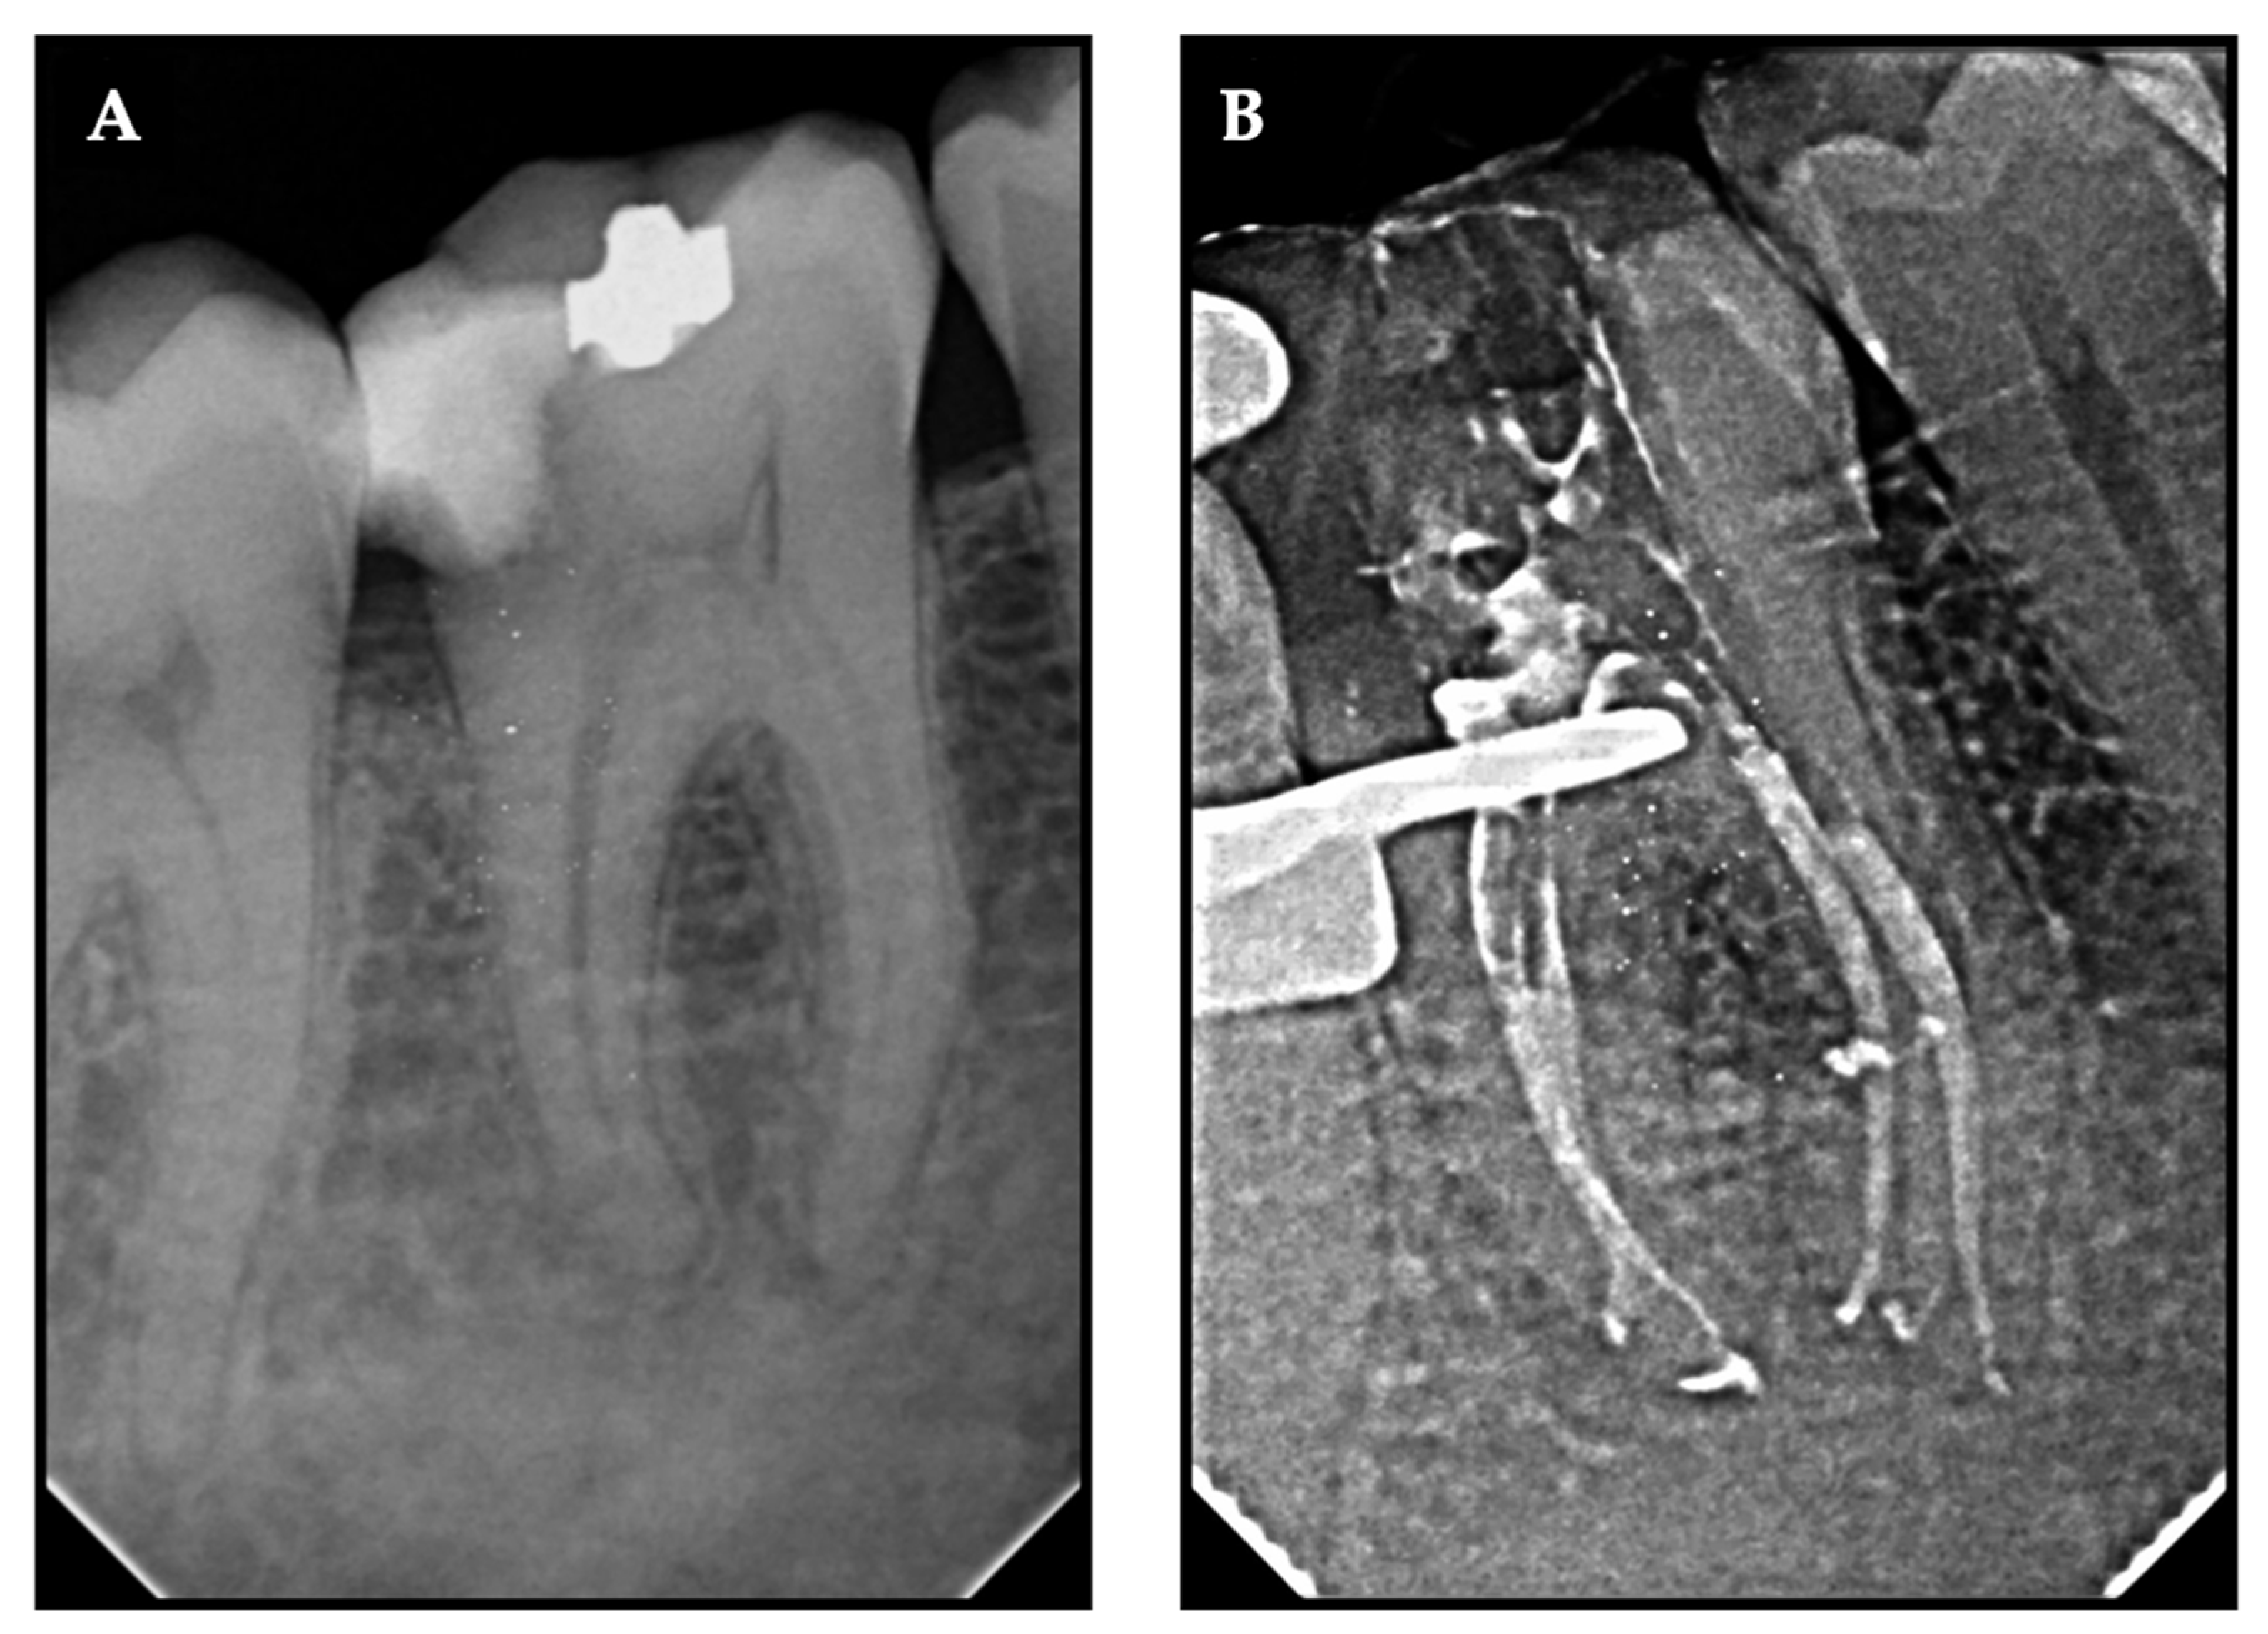

Figure 2. Representative radiovisiographs (RVGs) of pre-operative and post-obturation for XP-endo shaper plus sequence (mandibular second molar) (A,B) and full-sequence SAF (mandibular first molar) (C,D).

2.6. Root Canal Obturation